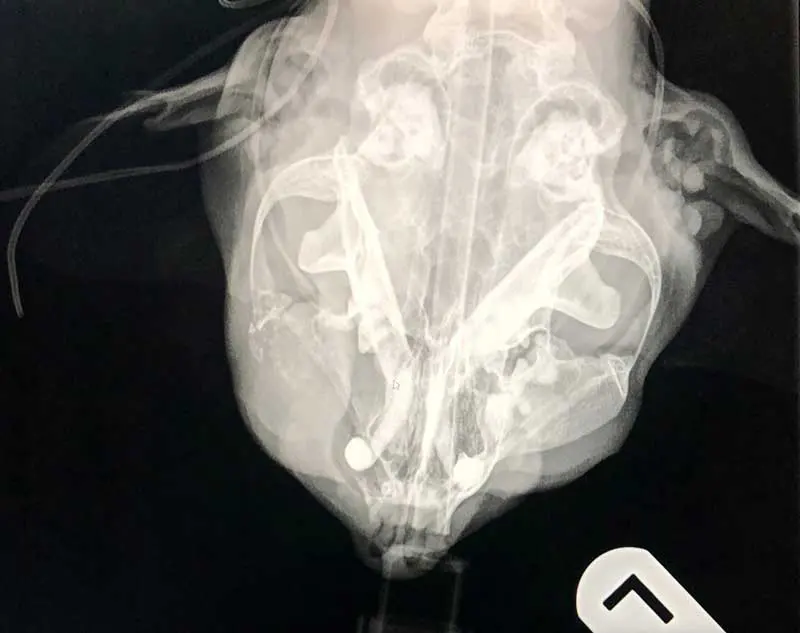

In more recent years, dental radiography has become a more common sight in first opinion practices, with the aim to identify tooth structures below the gingival margin, within the bone – pathology that remains undetected otherwise (Milella, 2022) – with recent studies showing that 27.8% of findings in dogs and 41.7% of findings in cats would be missed (Van Velzen, 2024).

With veterinary nurses already being able to perform thorough oral examinations, scale and polishes, record findings on dental charts and offer home care instructions, no reason exists why they cannot get involved with dental x-rays and be the ones taking the intra-oral dental radiographs. Although challenging at first, dental radiography is changing the landscape of first opinion dentals.